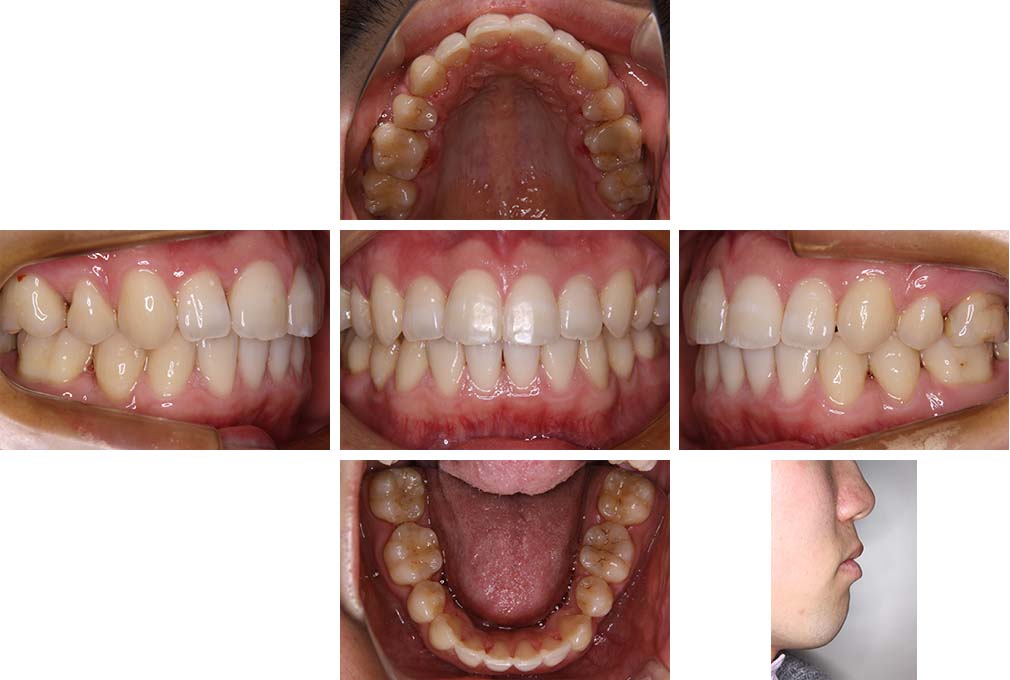

CASE:04

アングルⅢ級傾向を持つ叢生

初診時年齢 22歳

性別 女性

治療費の目安 105万円程度(治療開始時)

上顎右側犬歯が唇側に転位していることを主訴に県内歯科医院から紹介来院された。骨格的にはⅢ級傾向で上顎右側犬歯が唇側転位となり、側切歯が口蓋側に転位していた。下顎前歯が叢生になっていることも相まって上下の正中線は右側に大きくずれていた。アングルⅢ級傾向を持つ上下顎前歯部叢生と診断した。

上下顎小臼歯を抜歯していただき上顎舌側、下顎唇側マルチブラケット装置を使用して動的治療を行った。矯正用ゴムの使用など協力状態も良く、正中線の大きな移動があったのも関わらず2年10カ月で装置を撤去し保定へ移行した。保定移行後14年が経過し、ご息女の診察でご来院いただいていたことから、口腔内を拝見したが、下顎前歯のわずかなずれがあったものの大きな歯列の乱れはなく歯列は安定していた。動的治療期間2年10カ月間。

治療前

22歳6か月

治療後

動的治療期間2年10カ月間

25歳6か月

治療終了

動的治療終了後2年2カ月

28歳8か月

14年経過

動的治療終了後14年7カ月

40歳1か月